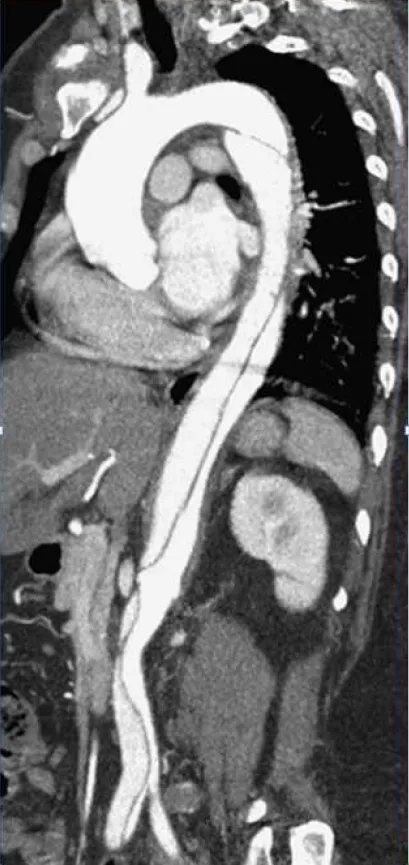

【107-2 醫學(五) 第20題】50歲男性病患主訴,有高血壓病史,未接受規則性之治療,3星期前有突發性撕裂性背痛至今仍舊無法緩解。電腦斷層顯示如下圖,下列診斷及治療何者錯誤?

詳解

破題關鍵

這題的解題核心在於辨識電腦斷層影像中的主動脈剝離類型,並結合病患病史判斷其屬於急性、亞急性或慢性,最後根據最新的治療指引來評估各選項的正確性。圖片中可見主動脈內膜剝離形成的雙腔結構,且剝離範圍始於降主動脈,是判斷主動脈剝離類型的重要視覺線索。

選項拆解